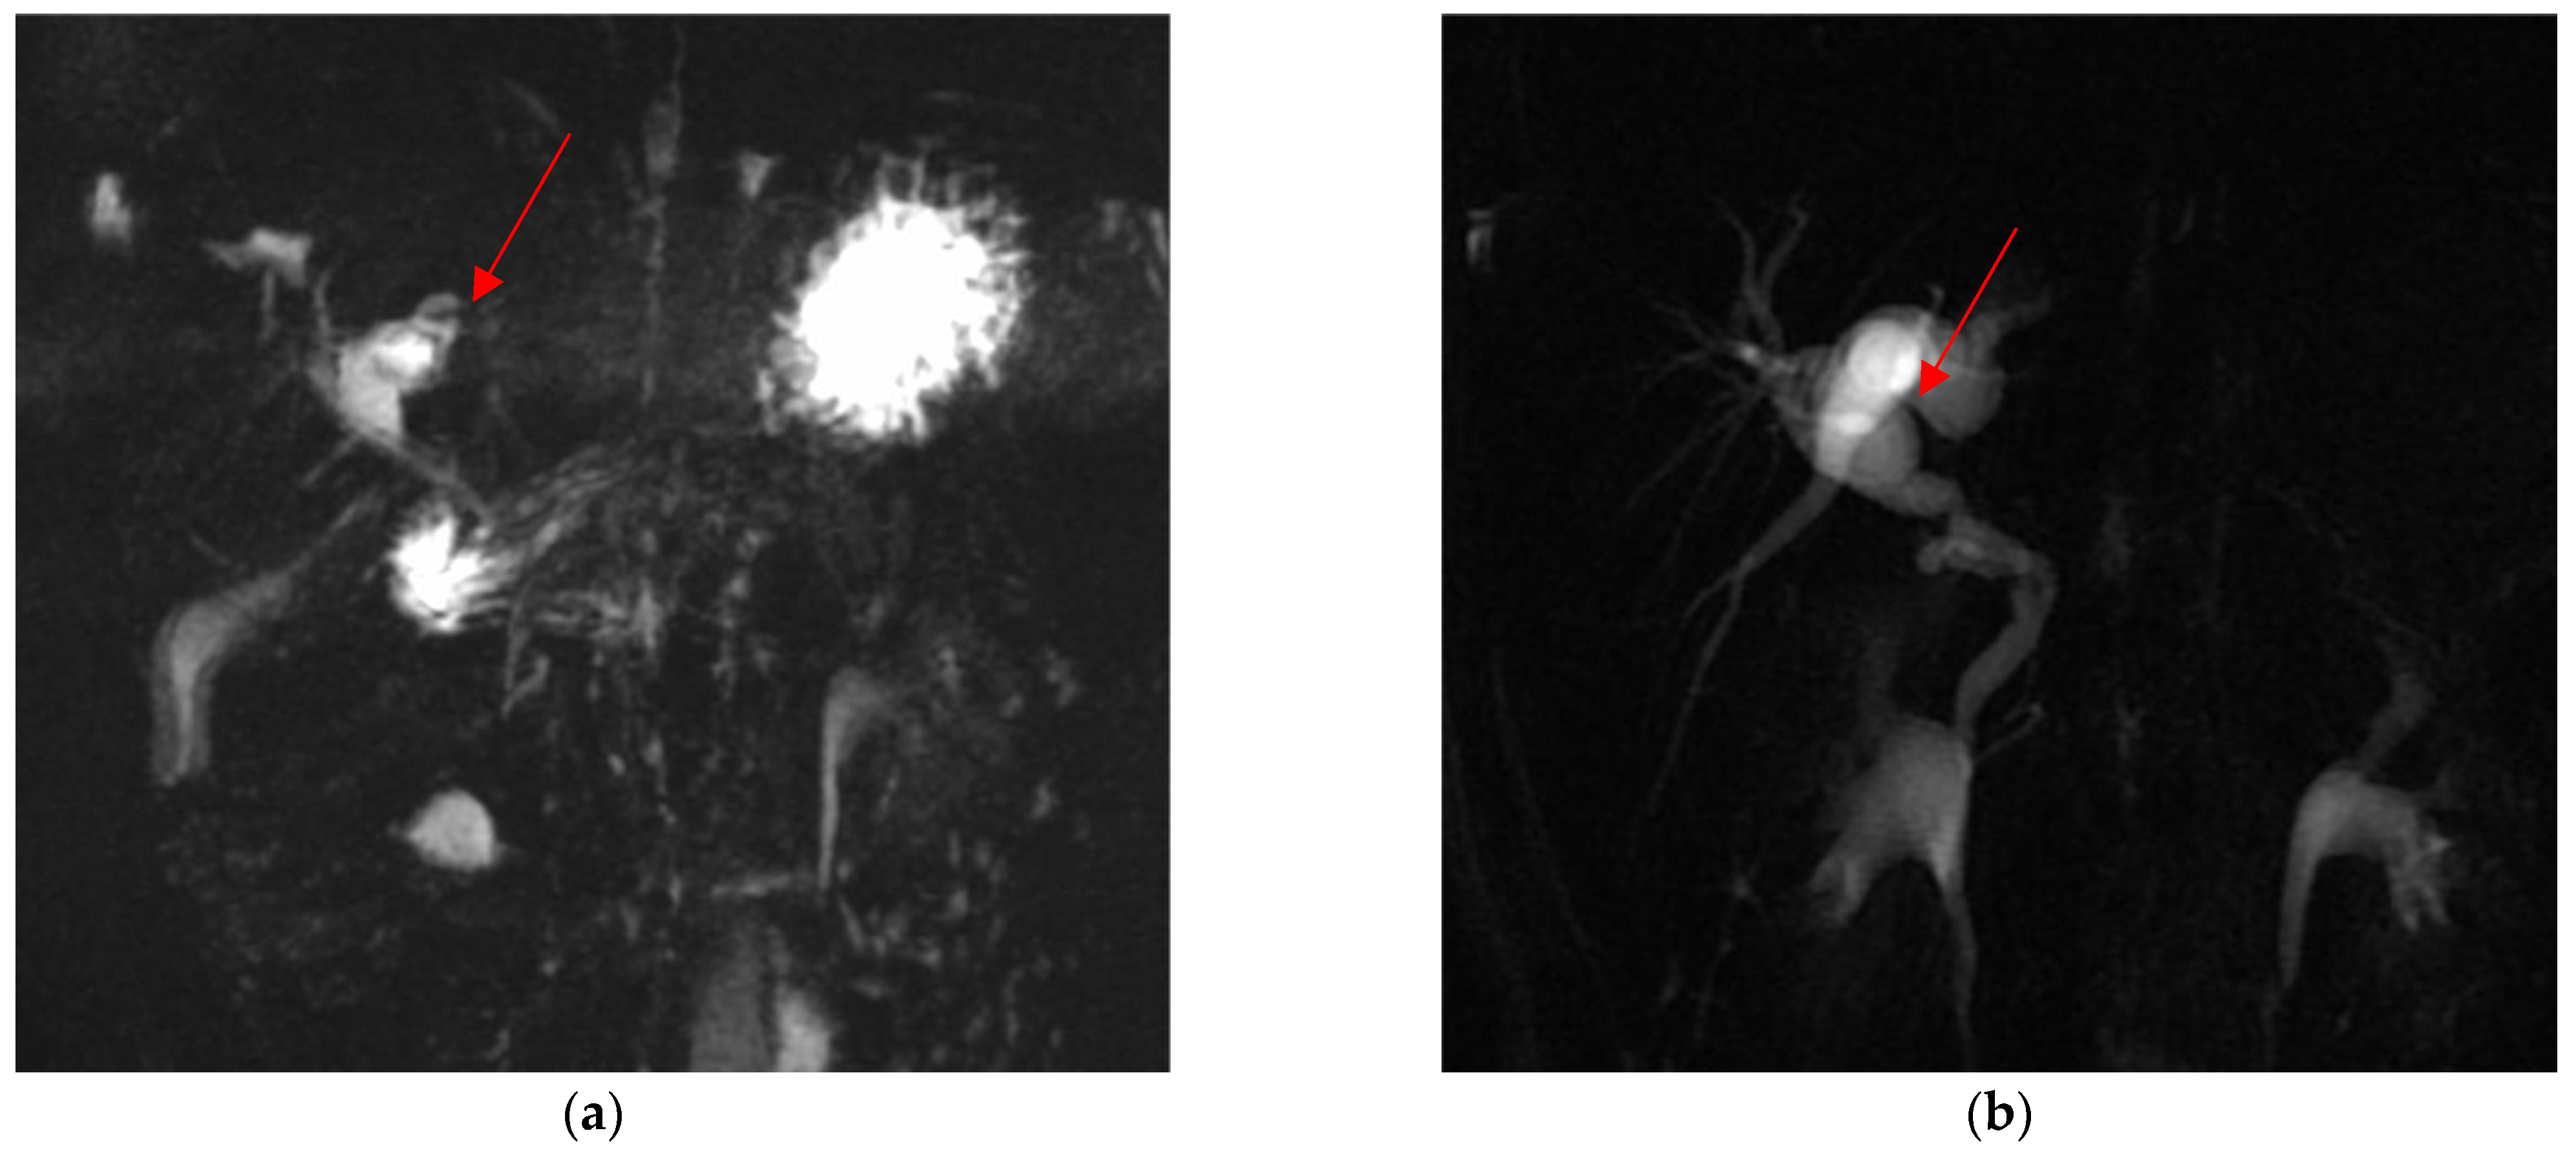

Out of these five difficult cases, laparoscopic cholecystectomy was totally completed in three cases (66.7%) and a subtotal cholecystectomy was performed in the other two (33.3%). There was no conversion to open surgery. Surgical difficulty was due to dysmorphic inflamed gallbladder with a dilated infundibulum and a tiny, convolute cystic duct (Figure 1a–c) in one case (20%); dense adhesions at the triangle of Calot due to the chronic inflammation in another case (20%) (Figure 2); an anomaly in the biliary tract anatomy in which the cystic duct projected into an aberrant right anterior hepatic duct and together they flowed into the common bile duct (20%) (Figure 3); and difficult trocar placement and reduced camera work due to the scoliotic attitude of two patients affected by Rett Syndrome (40%) (Table 2). None of these complex cases had Mirizzi syndrome or cholecystoenteric fistulas.

Figure 2.

Dysmorphic and dilated left hepatic duct (red arrow) in pre- (a) and post-operative (b) cMRI.